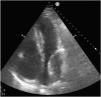

This is the case of an 80-year-old man with multiple cardiovascular risk factors admitted to the intensive care unit due to non-ST-segment elevation acute myocardial infarction. The coronary angiography performed reveals the presence of left main coronary artery and left anterior descending coronary artery disease. Revascularization is attempted through overlapping drug-eluting stent implantation (Fig. 1, blue arrow). Afterwards, the left circumflex artery is crossed with a guidewire (Fig. 1, red arrow). Procedure is uneventful. However, suddenly after the procedure the patient shows signs of heart failure. Transthoracic echocardiography confirms the presence of a 64mm×40mm mass—echolucent inside—with demarcated borders at left atrium lower level with a reduced size of such cavity compromising atrial filling consistent with left atrial wall hematoma (Fig. 2).